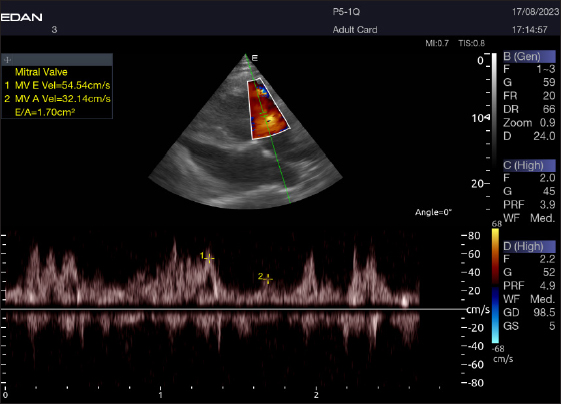

Left parasternal ultrasonography

The Mv E/A (Fig. 8), Tv E/A (Fig. 9), and maximum velocity of the aortic valve (Av Vmax) (Fig. 10) were all measured using pulsed-wave Doppler at LPSLAx in all camels. Two cases were observed with mild mitral regurgitation detected through continuous-wave Doppler, but the regurgitation was not considered significant (Fig. 11).

Fig. 8. Left parasternal longitudinal axis of a 16-year-old racing camel showing pulsed wave Doppler over the mitral valve (1=E wave and 2=A wave).